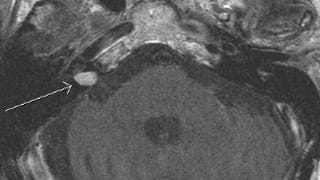

MRI of the Internal Auditory Canals with and without Intravenous Contrast

High-resolution MR imaging of the internal auditory canals and petrous temporal bones, as well as MR imaging of the entire brain, with and without intravenous contrast.

Thorough evaluation of the brain stem, 7th and 8th cranial nerves, membranous labyrinths, and temporal bones.

- Benign or malignant masses (vestibulocochlear schwannoma, facial schwannoma, facial nerve hemangioma, meningioma, metastatic disease, brain stem glioma, perineural spread of parotid malignancy, arachnoid cyst, epidermoid cyst, cholesteatoma, cholesterol granuloma, middle ear adenoma, paraganglioma, endolymphatic sac tumor, neurofibromatosis type II)

- Vascular lesions (vascular loop, aneurysm, vascular malformation)